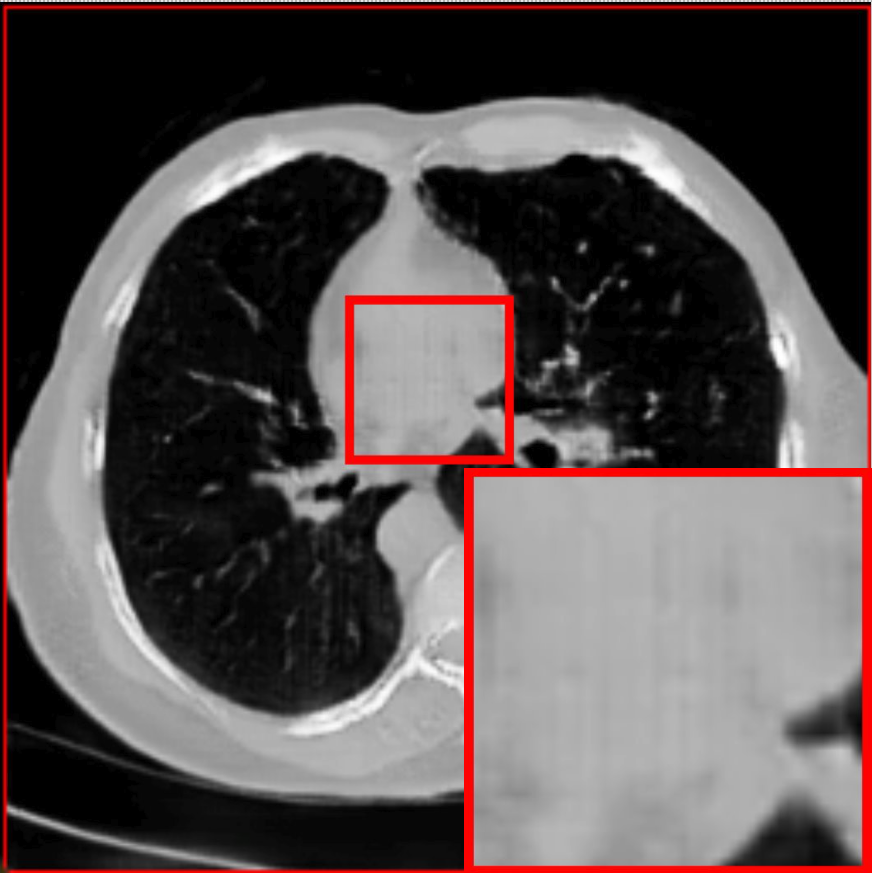

Figure 2: Qualitative comparison across axial (top row), sagittal (middle row), and coronal (bottom row) views. Columns correspond to different methods. MAISI-DDPM and MAISI-v2 in this figure are unconditional synthesis which do not use ControlNet or segmentation maps.

Qualitative Evaluation:

Figure 2 presents representative slices from the axial, sagittal, and coronal planes. GenerateCT (Hamamci et al. 2024) is a 2D model, so it lacks inter-slice consistency, leading to poor image quality in the sagittal and coronal views. MedSyn (Xu et al. 2024) produces noticeably blurry results with mosaic-like artifacts, such as region inside the red box. HA-GAN (Sun et al. 2022) generates visually sharp images but with mosaic-like artifacts, such as region inside the red box. Also, its voxel spacing is not available, which limits its applicability in real-world medical imaging tasks. Moreover, all three methods are restricted to synthesizing small anatomical regions. In contrast, both MAISI and MAISI-v2 are capable of generating high-quality 3D volumes that span larger body regions while preserving fine anatomical details and realistic structure.